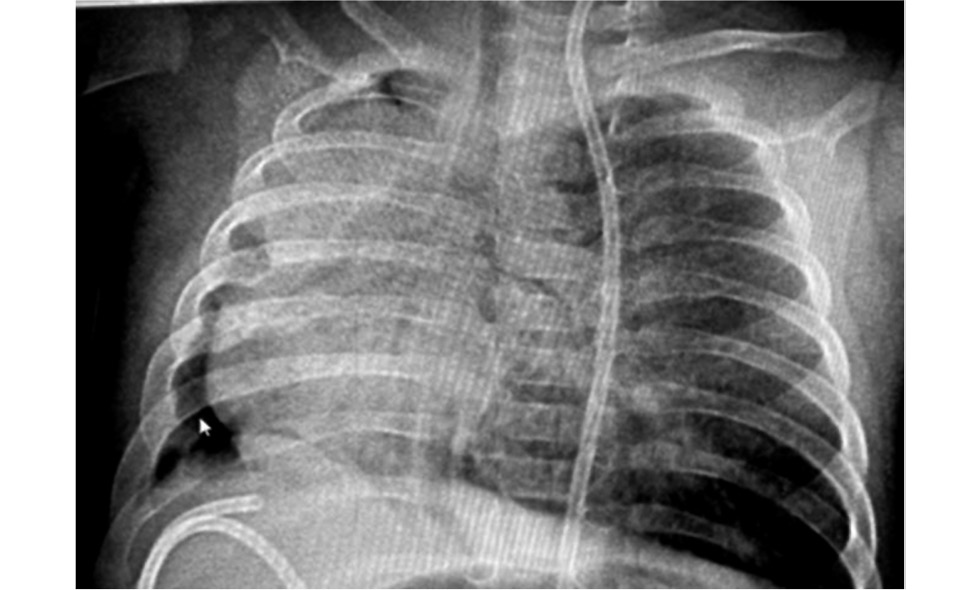

В динамике состояние было стабилизировано, получена положительная динамика со стороны лёгких, подтверждённая рентгенологически (рис. 2). На 17 сут жизни девочка была переведена на традиционную вентиляцию лёгких.

Рис. 2. Рентгенограмма органов грудной полости на 17 сут жизни: положительная динамика.

Fig. 2. X-ray of the chest organs on the 17th day of life: positive dynamics.

Через 2 сут клинический статус вновь ухудшился за счёт нарастания ДН, по результатам рентгенографии выявлен ателектаз нижней доли правого лёгкого (рис. 3).

Рис. 3. Рентгенограмма органов грудной полости на 19 сут жизни: ателектаз нижней доли правого лёгкого.

Fig. 3. X-ray of the chest cavity on the 19th day of life: atelectasis of the lower lobe of the right lung.